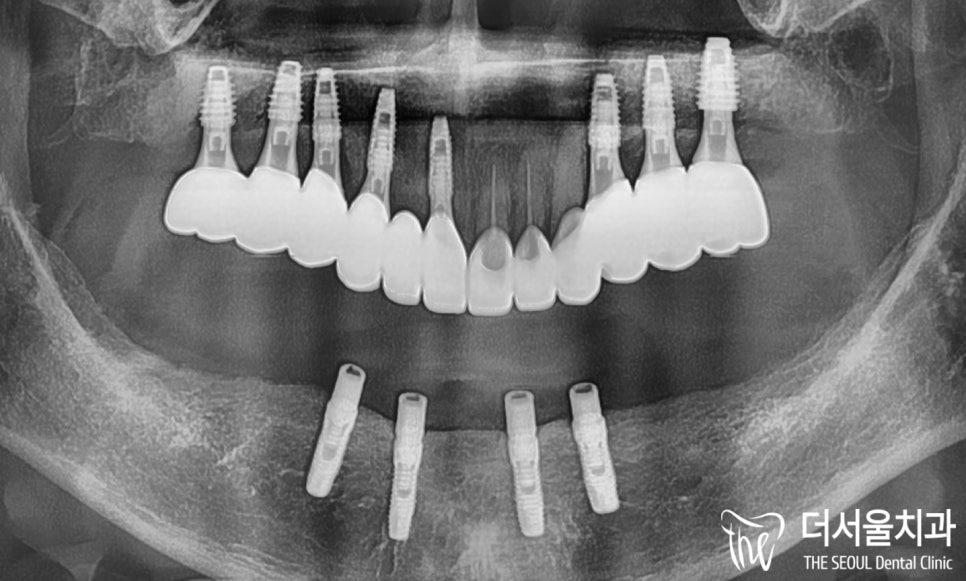

엑스레이로 한번 더 마지막 체크를 했습니다.

계획에 맞춰 좋은 결과를 얻었습니다.

뼈이식과 픽스처, 힐링 어버트먼트 세팅까지

모두 완료했습니다.

안정감있게 고정이 잘 되었네요.

이제 최종 보철 제작에 들어갑니다.